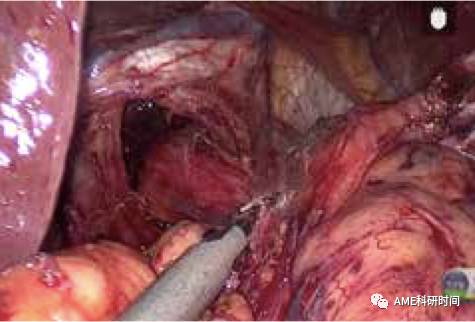

2 使用线型切割闭合器吻合

同上法离断空肠后,打开食管下端(如图43)、缝闭远端空肠(如图44),远端空肠距断端6 cm处对系膜缘戳一小孔(如图45),食管下缘打开一小孔,远端空肠上提,置入线型切割闭合器行食管空肠侧侧吻合(如图46),用线型切割闭合器(如图47)或手工缝合关闭共同开口(如图48)。空肠空肠吻合方式同前。

管型吻合器怎么用完全腹腔镜下全胃切除术后的消化道重建——7种食管空肠吻合方法_https://www.jmylbn.com_新闻资讯_第43张

图43 打开食管下端

管型吻合器怎么用完全腹腔镜下全胃切除术后的消化道重建——7种食管空肠吻合方法_https://www.jmylbn.com_新闻资讯_第44张

图44 缝闭远端空肠

管型吻合器怎么用完全腹腔镜下全胃切除术后的消化道重建——7种食管空肠吻合方法_https://www.jmylbn.com_新闻资讯_第45张

图45 空肠戳孔

管型吻合器怎么用完全腹腔镜下全胃切除术后的消化道重建——7种食管空肠吻合方法_https://www.jmylbn.com_新闻资讯_第46张

图46 侧侧吻合

管型吻合器怎么用完全腹腔镜下全胃切除术后的消化道重建——7种食管空肠吻合方法_https://www.jmylbn.com_新闻资讯_第47张

图47 闭合共同开口

管型吻合器怎么用完全腹腔镜下全胃切除术后的消化道重建——7种食管空肠吻合方法_https://www.jmylbn.com_新闻资讯_第48张

图48 缝合共同开口

注:本吻合方式,按照吻合的空肠蠕动方向可分为顺蠕动及逆蠕动吻合法两种。采用逆蠕动方法,可从空肠断端开孔与食管进行侧侧吻合,共同开口可用切割闭合器关闭。